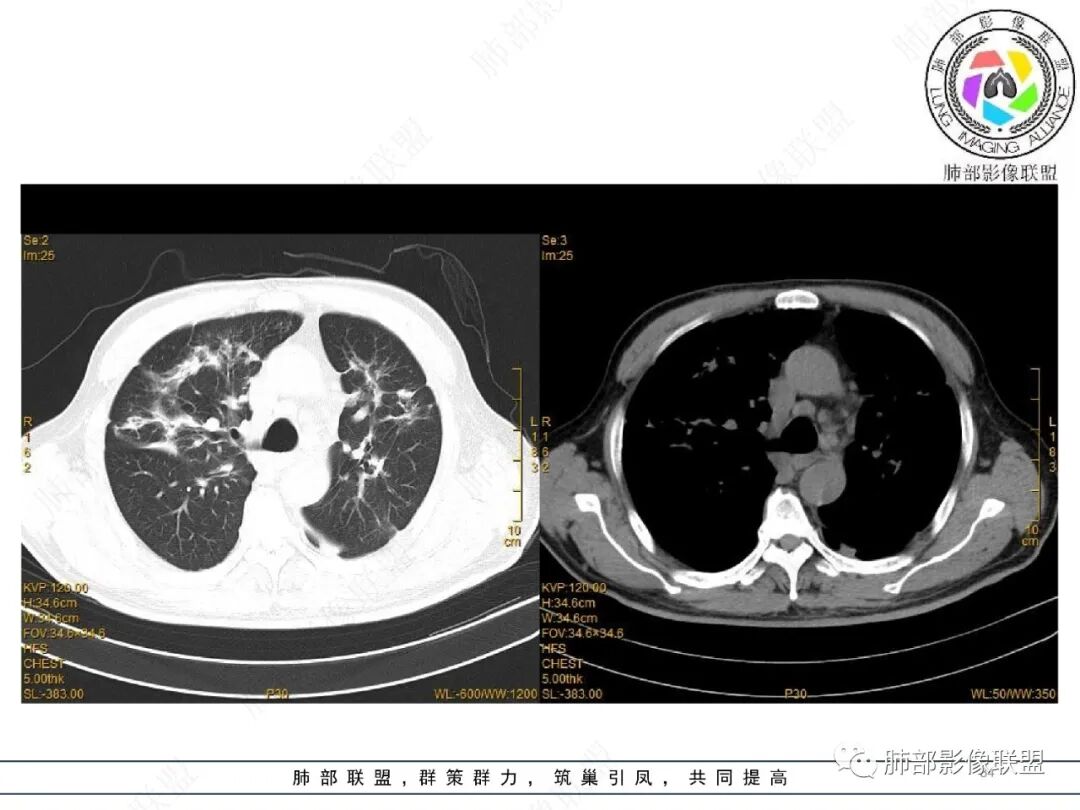

2022.2.17CT显示两肺中内带多发结节影、斑片影、条索影,部分病灶侧向融合与胸膜平行。部分病灶沿着支气管血管束分布、其内支气管稍扩张。部分病灶呈反晕征。大部分病灶边界显示清晰,部分病灶周围可见边界不清的GGO。2022.4.12CT显示两肺中内带多发结节影、条索状、条带状高密度影,边界收缩平直凹陷,大部分病灶沿着支气管血管束分布,亦有位于胸膜下侧向融合与胸膜平行的病灶。总体与第一次CT对比两肺病灶明显吸收。

老年男性,两肺多发病灶,整体呈OP样改变,至于是原发性还是继发性的OP,需要临床鉴别。此病例穿刺结果是隐球菌。该病例CT上缺乏隐球菌典型的“在那遥远的胸膜下,多个蘑菇兄弟,可以侧向融合呈长串状与胸膜平行”影像表现,更多是OP样改变,仅凭临床表现或影像资料诊断隐球菌难度比较大。当然也不除外二元论,导致隐球菌的影像表现被掩盖。